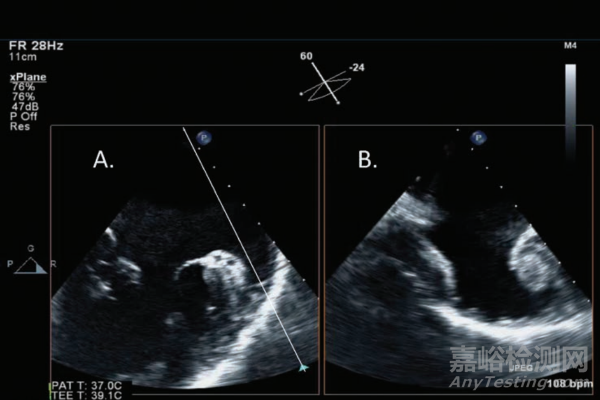

與二維超聲成像相比,三維超聲成像可以更全面的展示心臟的解剖與功能情況,同時(shí)提供更準(zhǔn)確的左心室(LV)運(yùn)動定量分析結(jié)果。一直以來主要制約三維超聲成像的技術(shù)瓶頸在于壓電晶體的性能以及信號數(shù)字處理速度,導(dǎo)致與二維超聲相比,圖像質(zhì)量下降和/或采集時(shí)間延長,一個(gè)典型的代表是將多個(gè)心動周期的二維圖像拼接成三維圖像所導(dǎo)致的偽影。最新的技術(shù)進(jìn)展,可在一個(gè)心動周期實(shí)現(xiàn)三維超聲成像,如下圖7所示[7],這一技術(shù)進(jìn)展不僅有助于提升LV運(yùn)動定量分析的準(zhǔn)確性,同時(shí)還會改善另外兩個(gè)臨床應(yīng)用:經(jīng)胸超聲的二尖瓣反流程度量化評估準(zhǔn)確性以及經(jīng)食道超聲的導(dǎo)管介入引導(dǎo),如圖8所示。

圖7:基于單心動周期采集和自動邊界檢測軟件得出的LV體積曲線示例。圖片引自文獻(xiàn)[6]

圖8:利用三維經(jīng)食道超聲技術(shù)行左心耳檢查是同時(shí)采集的兩幅正交平面圖像,圖像B與圖像A正交與A中白線所示位置。圖片引自參考文獻(xiàn)[6]